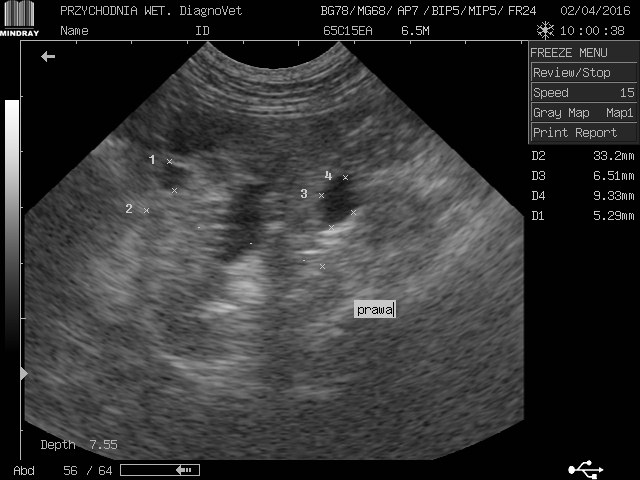

gracja1 Posted August 24, 2017 Posted August 24, 2017 Witam moja ukochana psinka gracja z wyników usg jest w bardzo kiepskim stanie nerki a praktycznie ich brak kwalifikują ja tylko do eutanazji jeżdżę od weta do weta i wszędzie żadnej pomocy.Gracja to piesek mieszany średniej wielkości trafiła do nas w ubiegłym roku ma zaledwie 2 lata.O chorych nerkach dowiedzieliśmy sie tydzień po przyjeździe jak do nas trafiła od początku objawy były ciągłe pragnienie wody i częstomocz decyzja tylko jedna jedziemy do weterynarza tam stwierdzono ze to zwykłe przeziębienie minęło parę dni brak poprawy u pieska powrót do weterynarza.Kazano zrobić badanie krwi moczu i wyszło kreatynina i mocznik podwyższony skierowano mnie na badanie usg tam potwierdziło chore nerki liczne cysty wokół diagnoza eutanazja natychmiastowa.Nie poddałam się minął rok z gracja od tamtej pory jest zemną bawi się biega kocha mnie nad życie lecz od paru dni dziwnie zaczęła się zachowywać jest osowiała mało zjada pije wodę wzięłam ja do weterynarza po diagnozie weterynarze są w szoku ze moja gracja żyję a na wieść o tym we dwoje zaczęli usg i to co zobaczyli to praktycznie brak nerek jedynie cysty do tej pory niewiadomo co tak naprawdę trzyma psa przy życiu i dziwią się ze on chodzi i biega w takim stanie a ja słyszę tylko w kółko pies do usypania zero szans zero leków absolutnie żadnej inicjatywy ze strony lekarza czy to normalnie dlatego jestem tutaj i opisuje swoja sytuacje a gracja leży przy mnie i nikt niepotrafi pomóc.Przesyłam skan usg krótko po przyjeździe gracji do mnie i pierwsze usg proszę o jakieś wskazówki do kogo jechać z kim porozmawiać bo siedzę i tony łez wylewam.Wyniki krwi z dnia 22.08.2017 Kreatynina 8.70mg/dl ,mocznik 300mg/dl 1 Quote